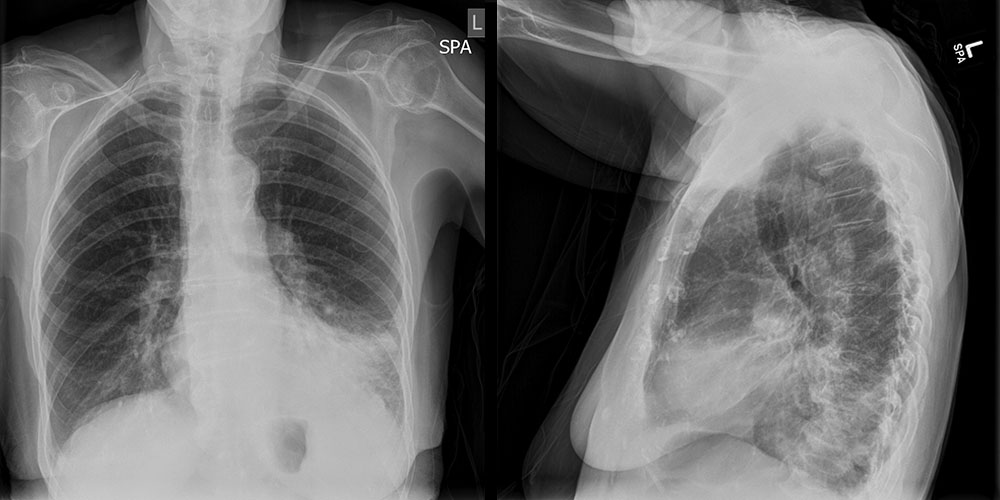

Lessons Learned: Several imaging features support the diagnosis of lobar pneumonia. (1) Airspace opacities (fluffy infiltrates with indistinct margins), which represent alveoli filling with exudate. (2) Air bronchograms (dark, streaky lines within the opacified area), which represent bronchi made more visible by surrounding alveoli filled with exudate. (3) Silhouette sign, which occurs when the opacified lung becomes a similar density to the diaphragm, heart border, or mediastinum, making them invisible. (4) Spine sign; the spine normally becomes darker when viewed from the top to bottom on a lateral chest radiograph. When there is an overlying infiltrate, the spine will appear whiter.

Socioeconomic Factors: (1) In a patient with a similar presentation, some centers may elect to begin with a CT scan. However, a chest X-ray is more cost-effective and minimizes radiation exposure.(2) In this case, a follow up X-ray may be considered to follow for resolution if there is a concern that this is a post-obstructive pneumonia secondary to an endobronchial cancer. However, if the patient is unlikely to follow up, we should consider performing a CT scan prior to discharge.(3) If a younger patient without comorbidities presents similarly, we may treat more conservatively by sending them home with antibiotics and close clinical follow up.